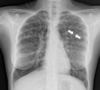

Esta es una radiografía de:

Signo del tranvía | (2 líneas paralelas)

87